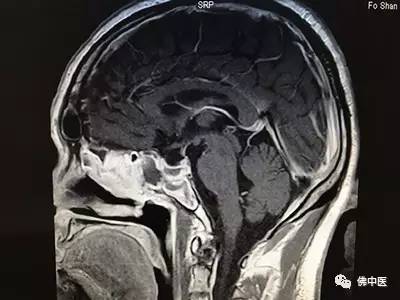

来自河源的刘先生十多年来饱受慢性顽固性头痛的困扰,近一年多来还出现了视力模糊的症状,经当地医院脑部核磁检查才惊现,原来脑部眼后方处有一个近3cm的肿瘤,正是肿瘤压迫才导致顽固性头痛和视力模糊。当地医生告诉刘先生要通过开颅手术切除肿瘤,风险很大,还容易引起严重的并发症。忧心忡忡的他经多方打听,得知佛山市中医院神经外科治疗脑部疾病享有较高声誉,果断地来到佛中医办理了住院手续。

术前

经验丰富的贾若飞主任接诊后,通过细致检查和阅片,确定刘先生患的是垂体大腺瘤,完全可以通过鼻腔微创手术切除肿瘤。术中,贾若飞带领专家团队成功为患者实施了内窥镜辅助下单鼻孔经蝶垂体瘤切除术。麻醉复苏后,患者激动地说:“我的头不痛了,感谢贾主任!”术后结合中医辨证施治以及优质护理,患者迅速康复,连连称赞佛中医不但环境好,专家实力更强,尤其是医护人员服务态度和敬业精神,让他充满了战胜病魔的信心。

术后